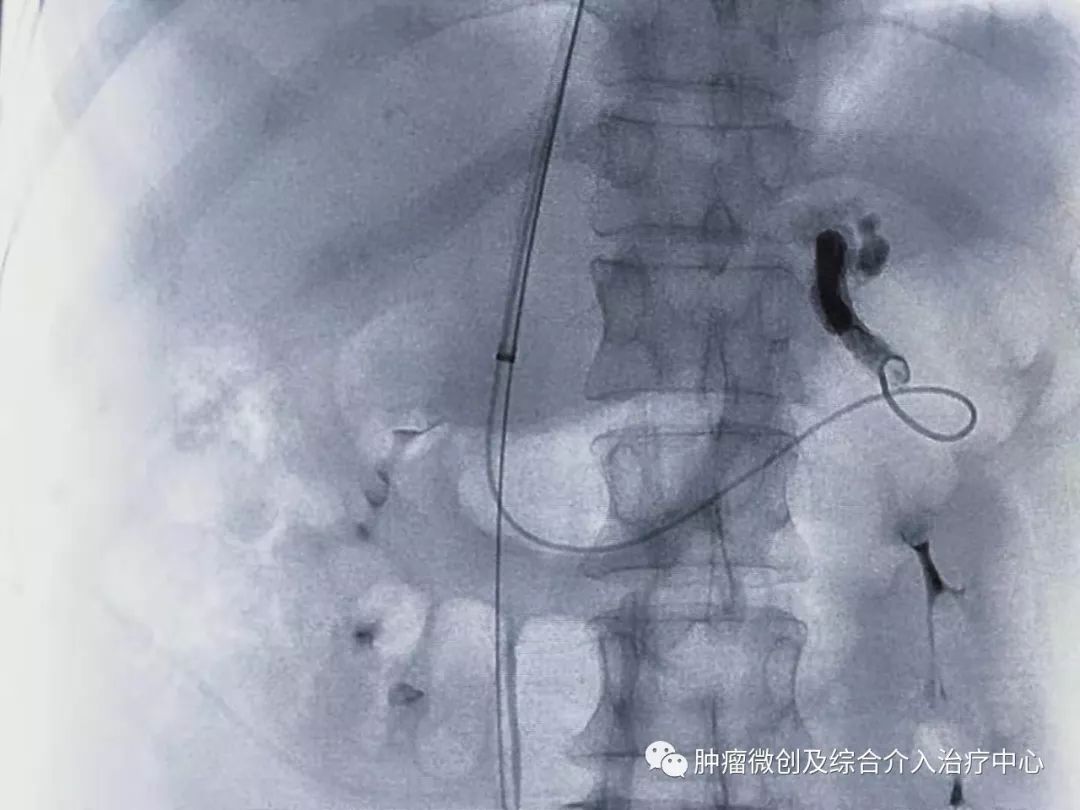

经过静脉穿刺进入门脉系统:

栓塞消化道出血责任血管:

球囊扩张静脉-门脉支架:达到门脉-体静脉充分分流目的

再次造影可见:门脉血流流向-体静脉达到分流目的,术前侧压力42,术后25,门脉压力明显降低,达到防止再次出血目的。